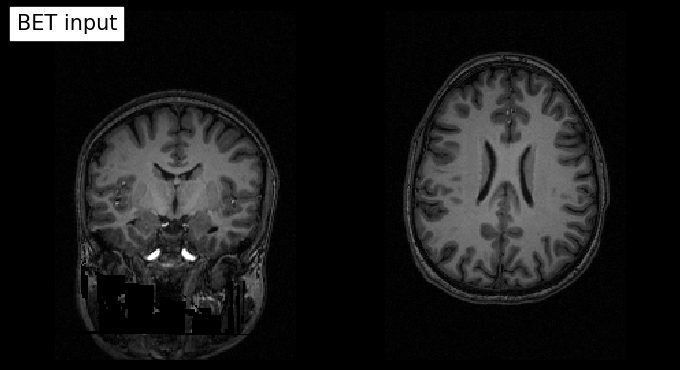

# Plot original input file

plotting.plot_anat(input_file, title='BET input', cut_coords=(10,10,10),

display_mode='ortho', dim=-1, draw_cross=False, annotate=False);

# Plot skullstripped output file (out_file) through the outputs property

plotting.plot_anat(res.outputs.out_file, title='BET output', cut_coords=(10,10,10),